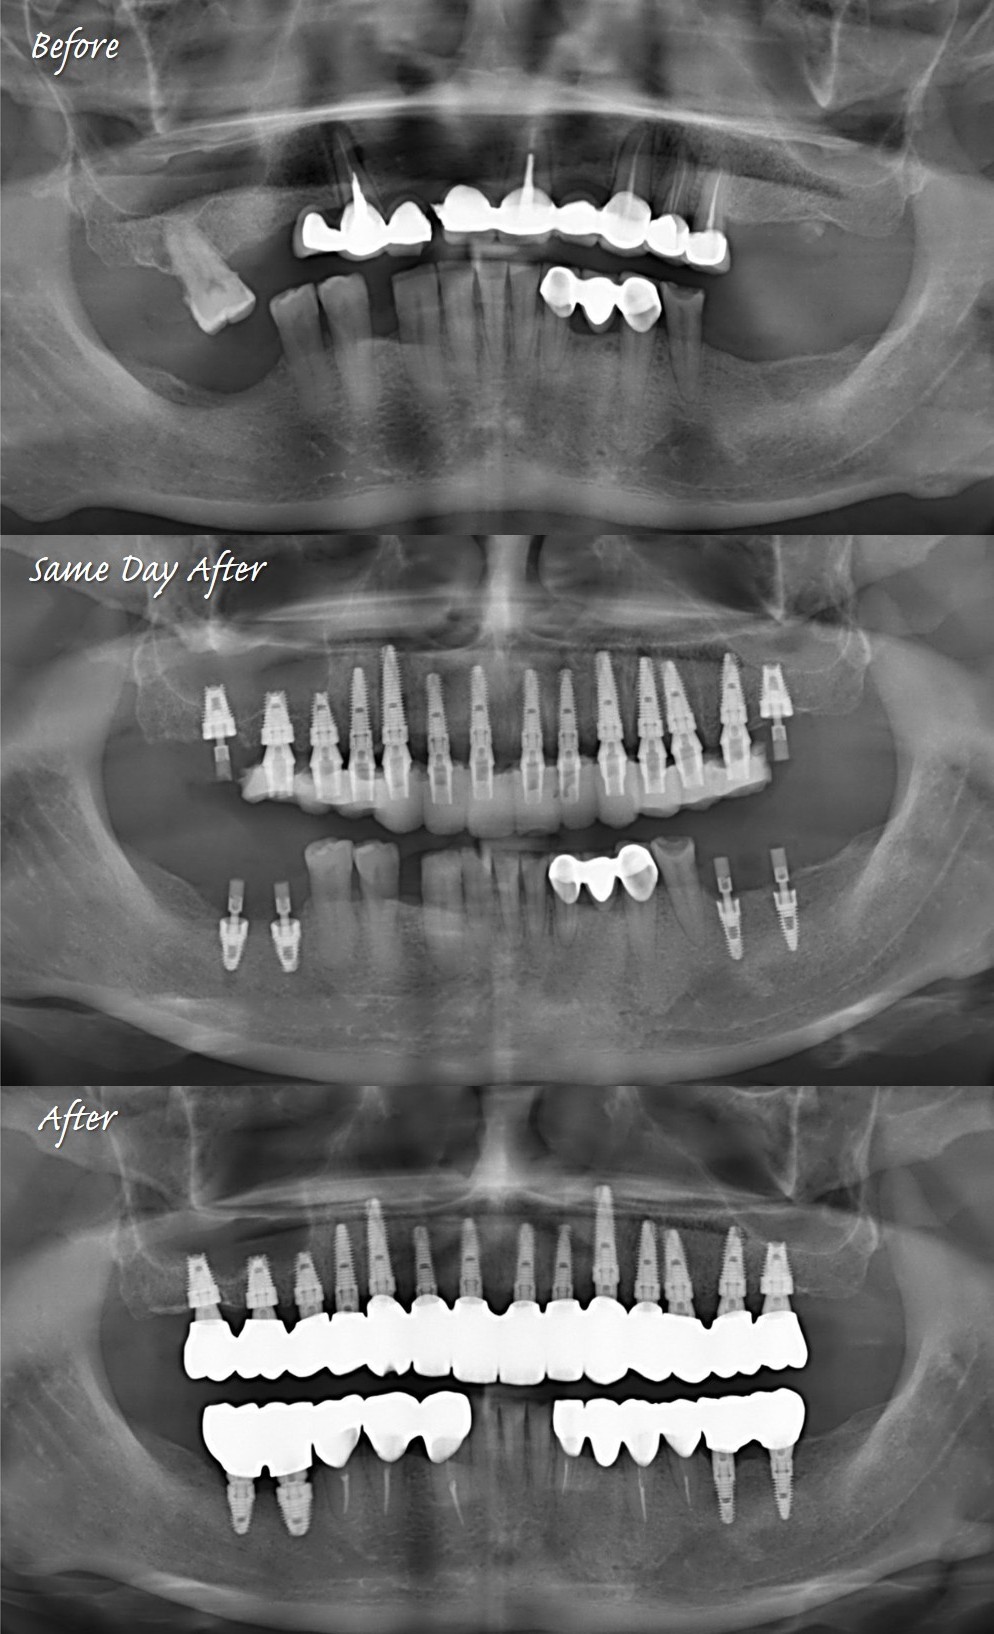

這樣的植牙方式,5 in 1:即拔即植加上同時補骨、推鼻竇與接臨時假牙出來。除了陳博士以外,也慢慢有優秀的學生做得到了。

與坊間全口重建常見到的all on X最不同的是,這才是最禁得起時間考驗的「一冠一釘」。紮紮實實又直挺挺的植體,而不是歪歪斜斜的植牙受力,真正的令人放心。